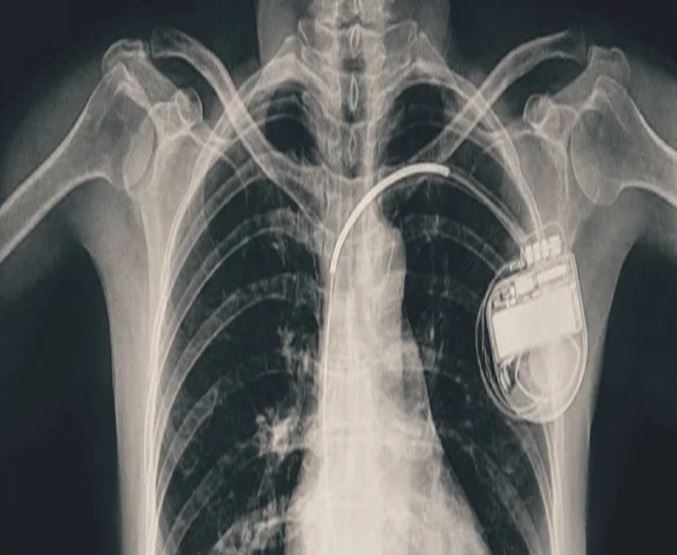

भोपाल। भोपाल मेमोरियल अस्पताल एवं अनुसंधान केंद्र (बीएमएचआरसी) के कार्डियोलॉजी विभाग ने एक दुर्लभ और चुनौतीपूर्ण चिकित्सा उपलब्धि हासिल की है। यहां 13 वर्ष की गैस पीड़ित आश्रित बालिका को इमरजेंसी में डुअल चेंबर पेसमेकर लगाकर उसकी जान बचाई गई। अब बालिका की हालत बेहतर है और उसे अस्पताल से छुट्टी दे दी गई है। यह प्रक्रिया सहायक प्रोफेसर डॉ. अमन चतुर्वेदी और उनकी टीम द्वारा सफलतापूर्वक की गई।

बीएमएचआरसी के कार्डियोलॉजी विभाग के सहायक प्रोफेसर डॉ. अमन चतुर्वेदी ने बताया कि यह मरीज जन्म से ही हृदय रोग से पीड़ित थी। तीन वर्ष की आयु में उसके दिल में छेद (congenital heart defect) का ऑपरेशन किया गया था। ऑपरेशन के बाद उसे हार्ट ब्लॉक हो गया यानी हृदय की धड़कन असामान्य रूप से धीमी हो गई। इसके कारण उसे चक्कर आना, आंखों के सामने अंधेरा छा जाना जैसी परेशानियां होने लगीं।हार्ट ब्लॉक की स्थिति में, बचपन में ही उसे एपिकार्डियल पेसिंग (epicardial pacing) डिवाइस लगाई गई। इस प्रक्रिया में पेसमेकर के तार हृदय की बाहरी सतह पर लगाए जाते हैं, जो आमतौर पर छोटे बच्चों में अपनाई जाती है, क्योंकि उनके हृदय का आकार छोटा होता है। इस डिवाइस की आयु लगभग 10 वर्ष होती है। डिवाइस की अवधि पूरी होने के बाद हाल ही में मरीज को फिर से वही लक्षण होने लगे। बीएमएचआरसी में जांच के बाद यह स्पष्ट हुआ कि अब उसे एक स्थायी और अधिक उन्नत पेसमेकर की आवश्यकता है। आपातकालीन स्थिति में टीम ने सफलतापूर्वक डुअल चेंबर पेसमेकर प्रत्यारोपित किया। इस जीवनरक्षक प्रक्रिया को अंजाम देने वाली टीम में कार्डियोलॉजी विभाग के सहायक प्रोफेसर डॉ. कपिलकांत त्रिपाठी, डॉ. नुपुर गोयल, मेडिकल ऑफिसर डॉ. अनुराग ठाकुर एवं अन्य सदस्य शामिल थे।

पेसमेकर एक छोटा उपकरण होता है, जो दिल की धड़कन को नियंत्रित करता है। यह दिल को सही गति से धड़कने में मदद करता है। सिंगल चेंबर पेसमेकर हार्ट के सिर्फ एक चेंबर को इलैक्ट्रिक सिग्नल देता है, जबकि डुअल चेंबर पेसमेकर दिल के दो भागों-ऊपरी (एट्रियम) और निचले (वेन्ट्रिकल) चेंबरों को दोनों को सिग्नल भेजता है, जिससे दिल की धड़कन और भी प्राकृतिक तरीके से चलती है। बच्ची के मामले में डुअल चेंबर पेसमेकर इसलिए लगाया गया क्योंकि उसकी स्थिति अधिक जटिल थी और बेहतर तालमेल के लिए दोनों चेंबर तक एकसाथ सिग्नल देना ज़रूरी था।

बीएमएचआरसी के चिकित्सकों का कहना है कि आमतौर पर पेसमेकर अधेड़ उम्र या बुज़ुर्गों को लगाए जाते हैं, लेकिन बच्चों में पेसमेकर लगाने के बहुत कम मामले सामने आते हैं। बच्चों या किशारों में ऐसा करना मुश्किल भी होता है क्योंकि बच्चों का दिल छोटा होता है, जिसमें उपकरण फिट करना कठिन होता है। साथ ही समय के साथ बच्चे का शरीर विकसित होता है, ऐसे में उपकरण का लंबी अवधि तक काम करना तकनीकी चुनौती बन जाता है। यही नहीं, पेसमेकर के तारों की लंबाई, फिटिंग और शरीर के भीतर उनकी स्थिति को भविष्य के हिसाब से बहुत सावधानी से तय करना होता है। बीएमएचआरसी की कार्डियोलॉजी टीम ने सभी सावधानी बरतते हुए मरीज को सुरक्षित रखा।